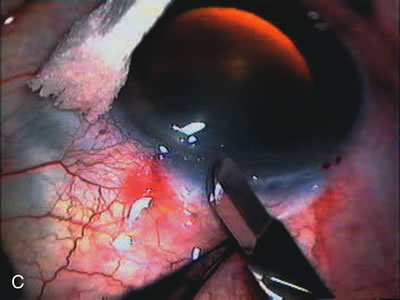

The inflammation associated with lens extraction at any site usually causes complete failure of a marginal functioning bleb. In addition, pressure reduction by medical means is usually minimal in these recalcitrant cases, and combined surgery is indicated. In the past, these cases were approached with large-incision ECCE, clear corneal cataract incision, and bleb revision. Drawbacks included those mentioned earlier for large incision clear corneal cataract extraction, and bleb revision is often associated with conjunctival buttonholes, wound leaks, subconjunctival hematoma, destruction of friable sclera, and associated hypotony. With the advent of modern-day cataract surgery, a phacotrabeculectomy is often possible adjacent to the failed filter (Fig. 7). The ability to combine cataract extraction with implant and filtration surgery all through the same small incision has greatly improved outcomes for patients with marginal preoperative filters. There are several other viable options in this case. If the surgeon elects to remove the cataract through a temporal clear corneal incision, the bleb may be revised or a new adjacent filter fashioned. As mentioned earlier, revising a failed filter is technically challenging. If the surgeon believes it is not feasible to revise the filter or fashion a new one, a glaucoma drainage implant is a reasonable option combined with temporal lens extraction.172

Fig. 7. Phacotrabeculectomy adjacent to a failed filter in cataractous eye. The ability to combine small-incision cataract extraction with trabeculectomy all through the same incision adjacent to the failed filter allows the surgeon to work in a familiar superior area. Avoiding incisions into the existing bleb decreases conjunctival buttonholes, hypotony, operating room time, and subconjunctival bleeding. A. Appearance of failed bleb with exposure of superior temporal quadrant gained with a corneal traction suture. B. Prepare a limbus-based conjunctival flap and a scleral flap. C. This bleb is at high risk to fail again justifying the need for MMC, 0.2 mg/cc applied on a pledget for 4 minutes. D. Insert the keratome and perform phacotrabeculectomy in the usual fashion.